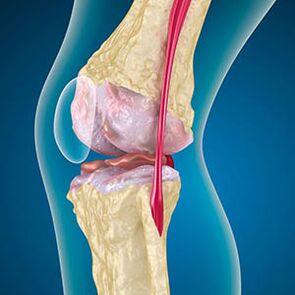

Arthrosis esetén a csontok széleit bélelő porc kopás vagy teljesen hiányzik. A sérült szövet nem a fájdalom forrása, mert nincs receptora. A közeli struktúrákban a gyulladás jellegzetes tüneteket okoz.

A test folytatja a sérült szövetek regenerációját, de a porc egyenetlenül növekszik. Ennek eredményeként szabálytalanságok alakulnak ki, amelyek megsértik az ízület más elemeit. Az osteofiták természetét a sima ízületi porc kompenzációja magyarázza. Egy másik verzió azt jelzi, hogy a "Spurs" növekedése Az izomgyengítés miatt az ízület mediálisan vagy oldalirányú stabilizálásának kísérletével jár.